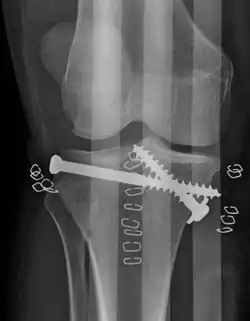

Fractura de meseta tibial

![]() Una fractura de meseta tibial severa | ||

La fractura de meseta tibial es una fractura de hueso en la continuidad del hueso que ocurre en la parte próxima a la tibia o espinilla llamada meseta tibial; afectando la articulación de la rodilla, la estabilidad y el movimiento. La meseta tibial es indispensable en el soporte del peso en el área localizada en la extremidad superior de la tibia y está compuesta de dos cóndilos cóncavos (cóndilo medial y cóndilo lateral) separados por una eminencia intercondílea y las zonas inclinadas al frente y detrás de ella. Se puede dividir en 3 áreas: la meseta tibial medial (la parte de la meseta tibial que está más cerca del centro del cuerpo y que contiene el cóndilo medial), la meseta lateral (la parte de la meseta tibial que está más alejada del centro del cuerpo y que contiene el cóndilo lateral) y la meseta tibial central (localizada entre las mesetas lateral y medial y que contiene la eminencia intercondílea). Dependiendo del patrón de la lesión, estas pueden estar enfocadas a la tibia o puede haber lesión de tejido suave significativa al igual que lesiones de meniscos y ligamentos en la rodilla. Aun así, una fractura de meseta tibial estándar implica ya sea una interrupción cortical, depresión o desplazamiento de las superficies articulares de la tibia proximal pero sin implicar una lesión a la cápsula o a los ligamentos de la rodilla.

El tratamiento está enfocado en lograr una articulación estable, alineada, móvil e indolora y en minimizar el riesgo de osteoartritis post-traumática. Para lograr esto, los médicos consideran planes operativos y no-operativos basados en el criterio formado por las características del paciente, la gravedad de la lesión, el riesgo de complicaciones, la depresión y desplazamiento de la fractura, el grado de lesión a los ligamentos y meniscos y el grado de riesgo vascular y neurológico. Para los primeros tratamientos, se debe realizar tracción de manera temprana en la sala. Puede ser tracción cutánea o esquelética. Depende del peso del paciente y de la estabilidad de la articulación. Se introducen tornillos de Schantz sobre el calcáneo y deben ser introducidos del lado medial al lateral. Una vez que la condición sea estable, el plan definitivo deberá reforzar la galvanoplastia y el tornillo de compresión de fijación.